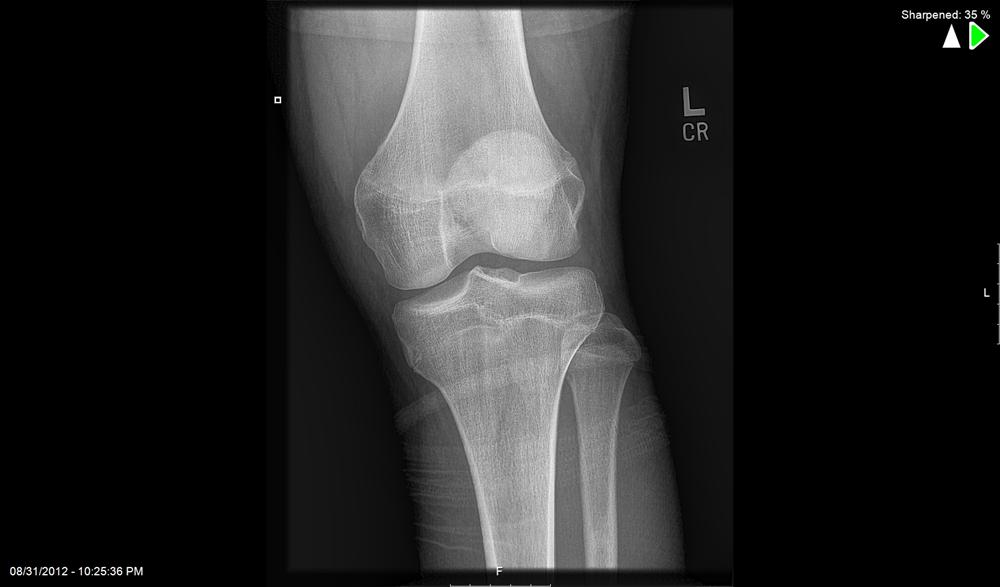

Knee Cartilage Defect . Articular cartilage defects of the knee comprise of a spectrum of disease entities from single, focal defects to advanced degenerative disease of. If you have cartilage loss in your knee, it's important to follow healthy. Knee cartilage is tissue that lines the ends of the bones in the knee joint, and its job is to make the knee bones glide over each other smoothly when we bend and straighten the knee. Cartilage injuries are quite common, especially among athletes, with a suggested overall prevalence as high as 36% in knees. Cartilage loss in the knee can lead to complications like bone spurs, cysts, and lesions. Cartilage lesions in large joints are common and can occur in isolation or in combination with bone deficiencies, ligament injuries, limb malalignment, and. Both types of knee cartilage can get torn and may cause symptoms like knee pain, buckling of the knee joint, and difficulty putting. Cartilage damage is most frequently seen between the ages of 15 and 30 or above the age of 50. Due to acute injury or general wear and tear and arthritis , knee cartilage defects can cause pain, swelling, loss of motion, and overall sideline you from life.

from www.orthobullets.com

Articular Cartilage Defects of Knee Knee & Sports Orthobullets